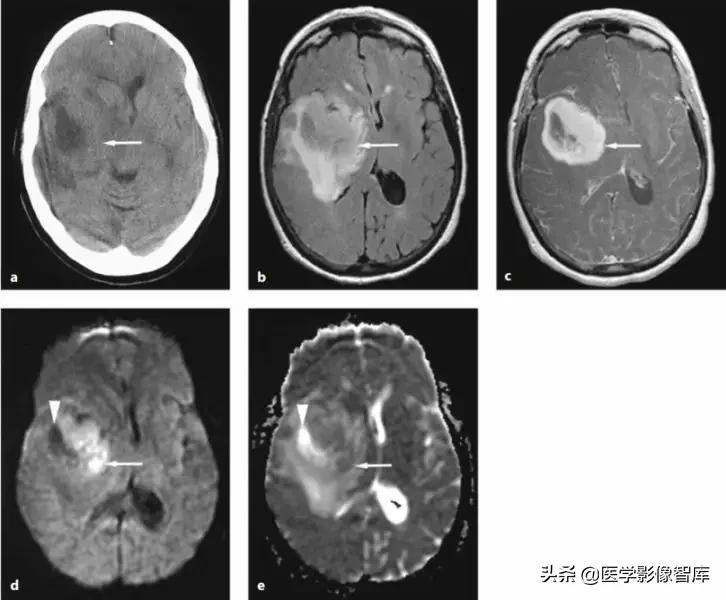

脑脓肿

我先放两张环形强化的图,大家可以猜猜哪个是脑脓肿,哪个是脑肿瘤。

图4 环形强化病灶对比

DWI是鉴别脑脓肿与高级别胶质瘤、转移瘤等良好手段。对于上图两个病例,其实加做一个DWI序列的话,就很好区分。左图患者DWI明显高信号,ADC图低信号,是脑脓肿;右图患者DWI低信号,ADC图高信号,是脑肿瘤。

图5 环形强化对比(脑脓肿 vs 胶质母细胞瘤)

脑脓肿主要是血源性感染,额、顶叶最常见,后颅窝小于15%,多位于灰白质交界处。一般为单发,多发少见(免疫抑制状态多见)。脓液表现为长T1长T2,FLAIR低信号,DWI高信号,ADC低信号;脓壁则包含了纤维成分,T1呈等/稍高信号,T2等/稍低信号,均匀环形强化(较光滑,深部薄,浅部厚);可以有子灶(卫星灶),破裂后形成小脓肿。